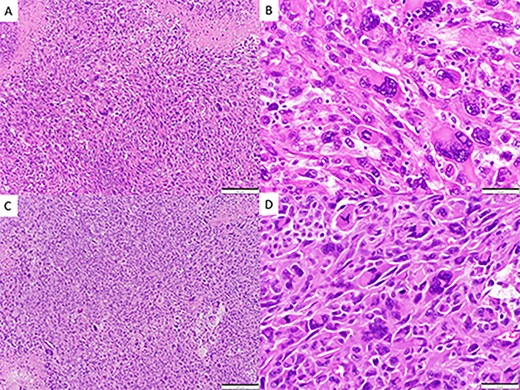

CASE

MRI scans indicating new metastatic lesions of the bilateral frontal lobes and right cerebral peduncle.